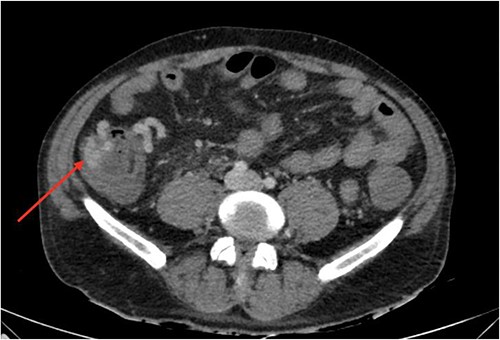

On gastroscopy, neither bleeding sources nor features of portal hypertension were identified. Subsequently, a large volume rectal haemorrhage occurred, resulting in severe hypotension and syncope. The patient was resuscitated appropriately and received a massive transfusion protocol. A CT angiogram revealed focal clustered varices travelling retroperitoneally abutting the caecal pole (Fig. 1), which communicated with a large branch of SMV in the right iliac fossa (Fig. 2).

Axial view of computerized tomography imaging in portal venous phase with arrow marking varices at the caecum.